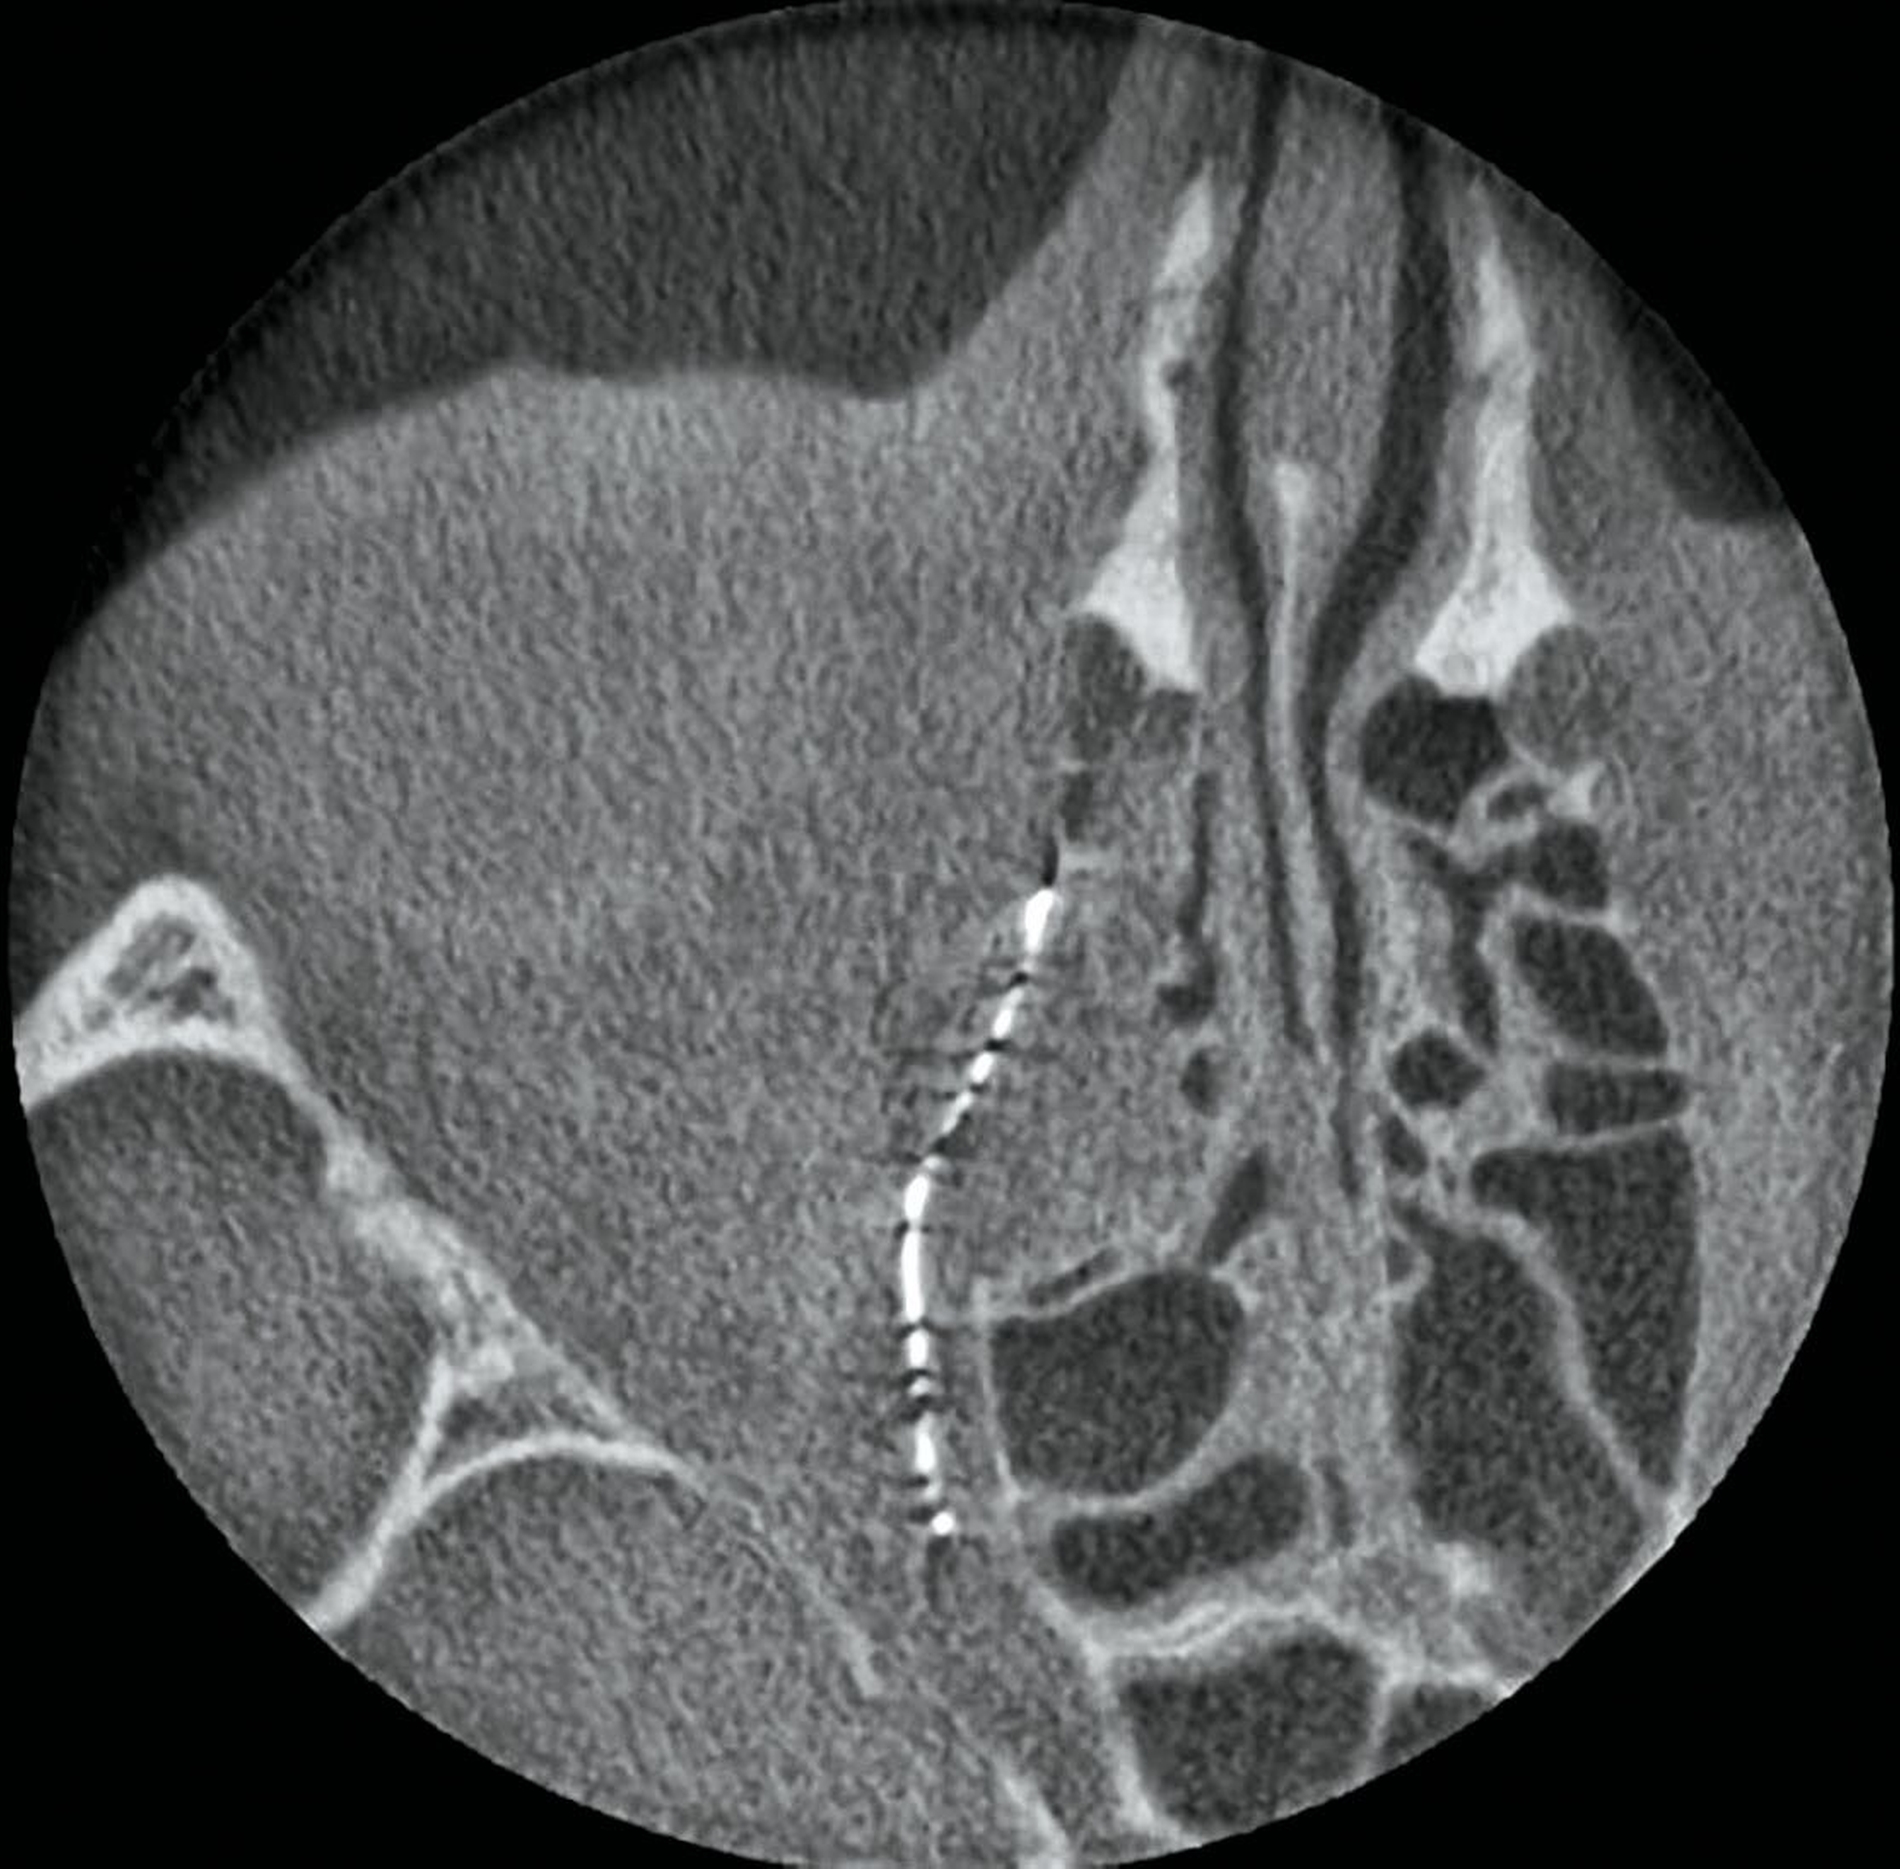

Zur Planung des PSI wurde während des stationären Aufenthalts eine hochauflösende Dünnschicht-CT durchgeführt. Im volldigitalen Workflow (IPS CaseDesigner®, KLS Martin Group, Tuttlingen) erfolgte die Planung und Herstellung des individuellen Orbitameshs: Die CT-Bilddaten wurden in ein dreidimensionales Modell umgewandelt, das die anatomischen Strukturen, einschließlich der Fraktur und der umgebenden Gewebe, detailliert abbildete. Basierend auf diesem Modell wurde das patientenspezifische Implantat digital entworfen, mit besonderem Fokus auf der Wiederherstellung der natürlichen Form und Funktion der Orbitawand sowie auf der Gewährleistung eines optimalen Halts (Abbildung 2).